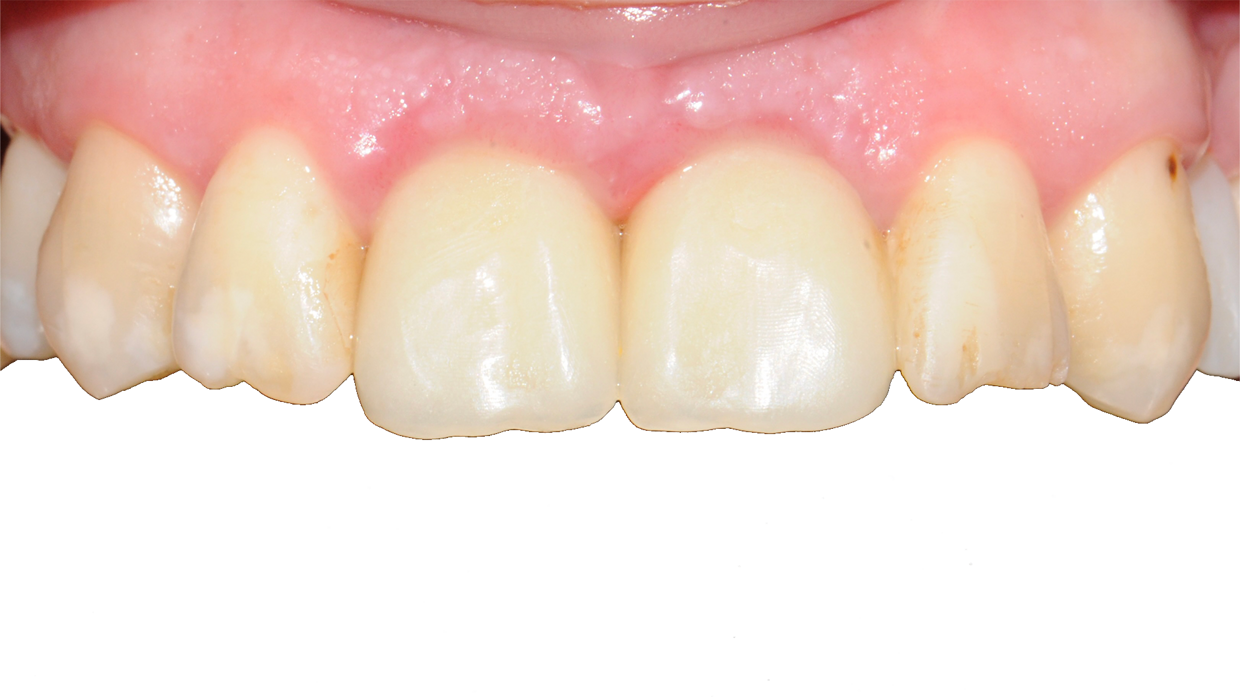

Il posizionamento degli impianti è stato pianificato prima dell'intervento su un software dedicato. In un'unica seduta, dopo l'estrazione degli elementi dentari compromessi, sono stati immediatamente inseriti gli impianti nella posizione pianificata, grazie alla realizzazione della dima chirurgica. Per ridurre il riassorbimento osseo a lungo termine e garantire quindi una maggiore resa estetica (vista la zona d'intervento), la chirurgia è stata eseguita con una particolare tecnica denominata: Socket Shield Technique.